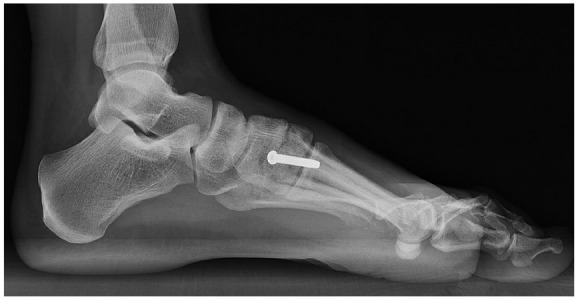

Methods: This study included patients who had a nondislocation Lisfranc injury with a proximal first webspace (between the medial cuneiform and second metatarsal base) diastasis of 2-5 mm, and underwent either a primary ORIF or primary arthrodesis. Preoperative weightbearing radiographs were reviewed to confirm subtle Lisfranc injuries. Of the 73 patients who met the inclusion criteria, 41 received a PA and 32 received an ORIF. Treatment selection was based on surgeon preference. Patient-reported outcomes via PROMIS scores were collected preoperatively and at least 2 years postoperatively. Subsequent procedures were also recorded.